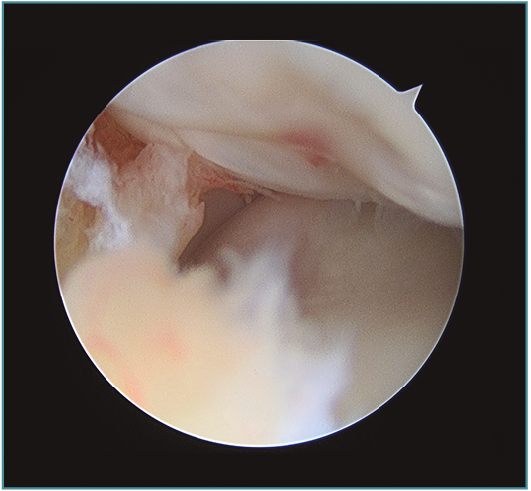

Los portales más adecuados son el anteromedial proximal para la óptica y el anterolateral, el anterolateral proximal y el mediolateral directo o soft-spot (Figura 4) como portales de trabajo. Los portales anteromediales permiten una excelente visualización de la cámara anterior, de la superficie articular de la cabeza radial, del cóndilo humeral, de la apófisis coronoides y de la cápsula anterior y lateral (Figura 5). A este nivel suelen observarse la gran mayoría de los cuerpos libres articulares que en ocasiones se encuentran en la zona lateral y posterior del codo (Figura 6).

Figura 5. Imagen artroscópica de defecto condral en porción anteroinferior de capitellum. Óptica en portal anteromedial proximal.